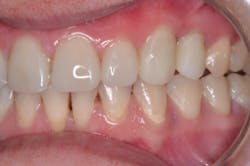

Using a Microcopy XF flame-shaped diamond, I opened up any overfilled embrasures, which required minimal effort thanks to a detailed matrix. Using QwikStrip serrated and polishing strips, I separated each of the teeth proximally and polished them. As anticipated, the proximal contacts for teeth Nos. 5–12 were light. To tighten the contacts post-operatively, I left the centric occlusal stops on Nos. 6–11 lighter than the occlusal stops of the posterior teeth (figure 7).

At the post-operative visit two weeks later, the contacts were perfect, and I achieved anterior disclusion in all excursions. No other refinement of the restorations was needed other than polishing of the surfaces, which required minimal effort. Activa has a chameleon effect that blends shades and reflects adjacent hues to create a natural esthetic.

Although four-year cases with Activa have been reported, only time will tell what the longevity of this case will be. So far, the case is at six months and counting confidently (figures 8 and 9). The durability of Activa has been reported in the literature. A patented, rubberized-resin molecule in the resin matrix absorbs shock and stress, and provides unique flexural strength that resists chipping and fracture. A far more expensive option that requires laboratory-fabricated porcelain crowns might provide a more esthetic result, but it was not a viable possibility in this case. The esthetic outcome achieved with this direct restorative technique is very good, and we know we did the right thing for this particular patient.